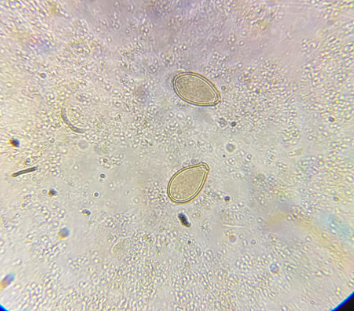

enterobius vermicularis jaja

trichuris trichiura jaja